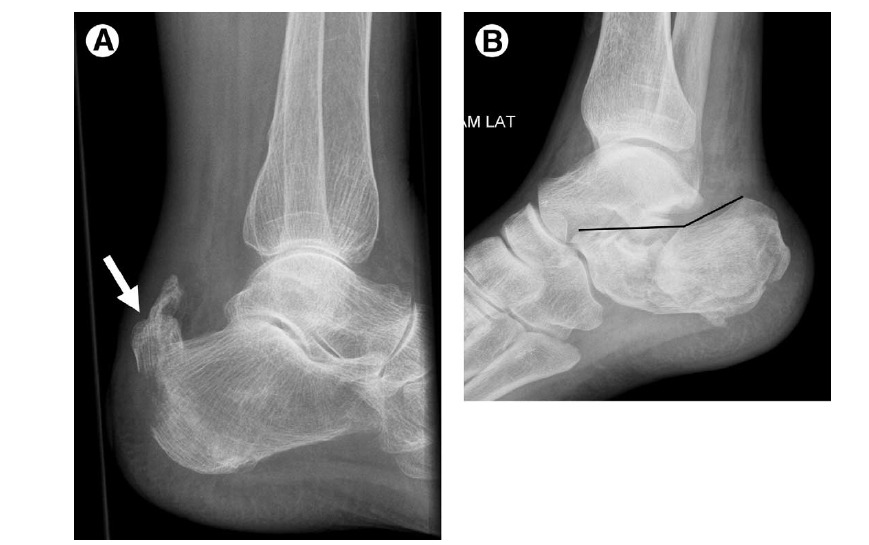

Figure 7 Calcaneal fracture.

(A) Achilles avulsion. Along with anterior process fracture depicted in Fig. 5E and extensor digitorum brevis avulsion fracture shown in Fig. 5B, Achilles tendon avulsion (arrow) is classified as an “extraarticular” calcaneal fracture. This fracture is more common in diabetic patients and patients with renal osteodystrophy.

(B) Joint depression-type fracture. Resulting from axial load injury, the “joint depression type” is the most common of the “intraarticular” calcaneal fractures. The talus is driven into the calcaneus, displacing the subtalar articular surface into the calcaneal body, flattening Boehler’s angle (lines), and typically creating an anteromedial sustentaculum fragment

and a posterior tubercle fragment, with varying degrees of comminution and medial-to-lateral widening. The “tonguetype

fracture” is described when a curvilinear fragment extending to the posterosuperior calcaneus is rotated downward.